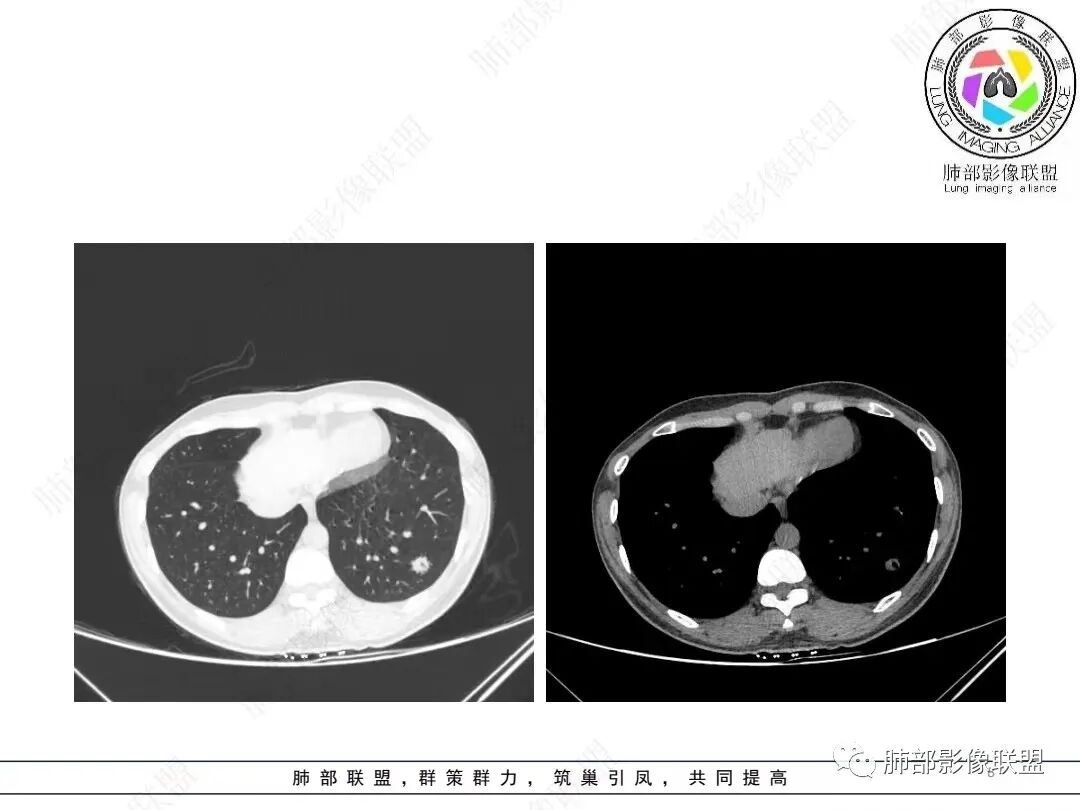

1、临床特点: 37岁女性,体检发现肺结节,2年前有甲状腺腺瘤手术史。实验室无阳性发现。

2、影像特点:左肺下叶类圆形结节影,周围可见多发细小毛刺,浅分叶,张力不高,未见胸膜牵拉。病灶内隐约见空泡影(未提供CT值),近端部分血管呈杵状增粗,可疑脐凹征。增强后实性部分有轻度强化。外围病灶,与支气管关系不明确。

4、病例小结:中青年女性偶然发现结节,表面欠光整,内部空泡,不均匀强化,边缘分叶毛刺等都具有影像学上的恶性征象,正如大多数老师所分析与肺腺癌较为符合。部分肺部肿瘤年轻化,尤其是肺腺癌等应当引发我们高度关注。